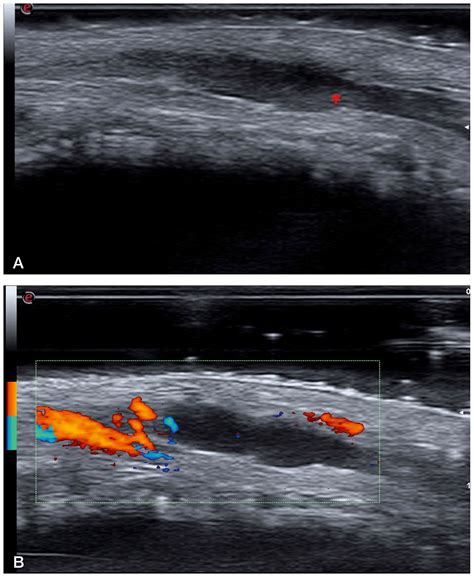

Ultrasound To visualize the affected vein and assess the presence of a blood clot.